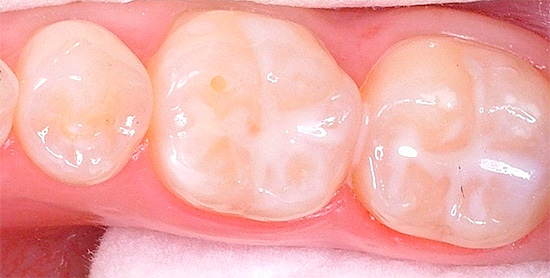

La seguente foto mostra chiaramente che la carie delle fessure è localizzata principalmente nella parte centrale della superficie masticatoria del dente. Se la malattia non è iniziata, la radice e il collo non sono interessati:

Un buon metodo di prevenzione è sigillare le fessure: sono riempite con un composito liquido, che quindi indurisce e impedisce ai batteri di accedere allo smalto dei denti. Sostanze attive vengono aggiunte al materiale, che rimineralizzano e rafforzano ulteriormente lo smalto.